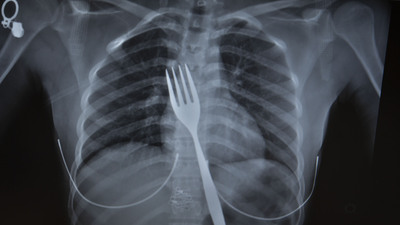

Söke'de yaşayan yabancı uyruklu E.E (18), yemek çatalı yuttuğu şikayetiyle ambulansla Aydın Adnan Menderes Üniversitesi (ADÜ) Hastanesine getirildi.

Burada röntgeni çekilen hastanın yemek borusunda 18 santimlik çatal olduğu tespit edildi.

Vakayı ilk duyduğunda şaşırdığını anlatan Edizsoy, "Büyük bir çatalın tamamen yutulması şeklinde ortaya çıkan bu vakayı ilk duyduğumda doğru olmadığını düşündüm. Hasta 18 yaşında ve yabancı uyrukluydu. Türkçesi biraz zayıf olduğu için belki de yanlış anlaşılmalar olabileceğini düşündük. Ama hastanın filmini çektiğimizde gerçekten bir çatalın yemek borusunda olduğunu gördük" dedi.